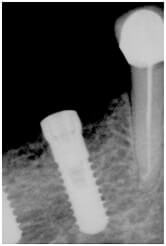

Cliché radiographique d'un implant parfaitement ostéo-intégré.

Après la phase opératoire, il y a la phase "d'ostéo-intégration". C'est la période pendant laquelle le tissu osseux cicatrise autour de l'implant, en l'enserrant dans ses mailles. D'une durée moyenne de 4 à 6 mois, cette phase est essentielle pour réunir tous les facteurs de réussite. Pendant, cette période, la zone concernée est au repos absolu ; l'implant est en nourrice et ne doit surtout pas être "mis en charge", sous peine de devenir mobile et de conduire à l'échec du traitement.

Dès qu'un implant est posé, une réaction de l'organisme démarre au niveau cellulaire pour fabriquer des mailles osseuses autour de l'implant et permettre ainsi sa bonne tenue. La période d'ostéo-intégration dure habituellement entre 3 et 6 mois.